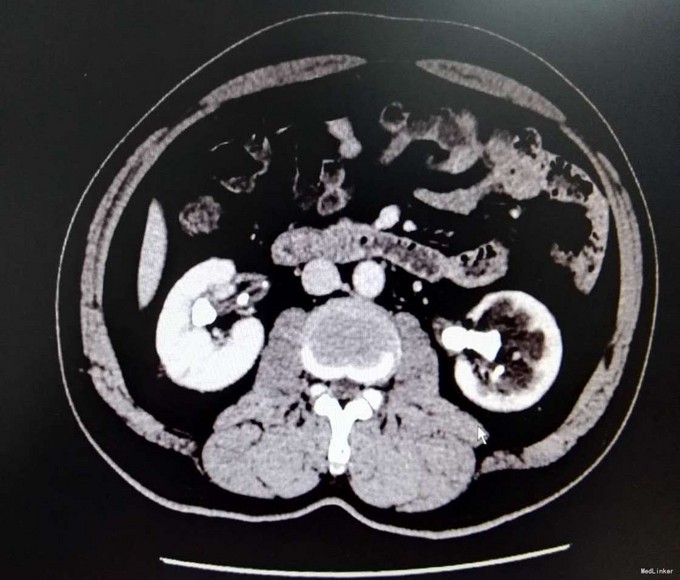

3、查体:未见明显阳性体征 4、辅助检查:外院平片:双肾多发结石;我院CTU:双肾多发结石,左侧肾盂输尿管连接处结石,并双肾积水,左肾明显,双侧肾盂、输尿管炎症。

5、诊断:肾结石(双肾多发结石) 6、治疗:入院后完善相关检查,双肾CTU:双肾多发结石,左侧肾盂输尿管连接处结石,并双肾积水,左肾明显,双侧肾盂、输尿管炎症。排除手术禁忌症后行左侧PCNL术,术后恢复良好,拔出肾造瘘管后,先出院休息,2周后返院进一步治疗